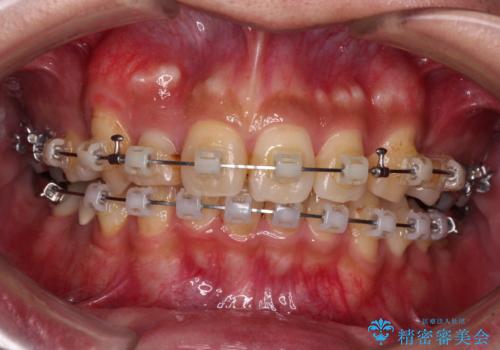

- クリアブラケット

- 2年8ヶ月

補助装置を併用することで効率的に八重歯や正中位置の改善を達成することができました。